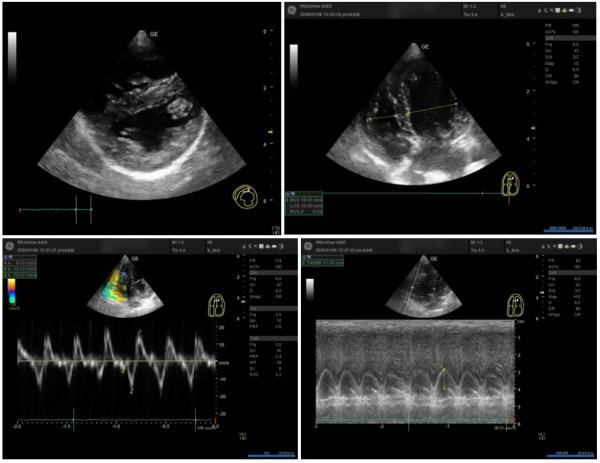

② RV(우심실)의 구조적 변화와 기능

우심실의 압력이 높아지면 좌심실을 압박하게 됩니다.

IVS Flattening (심실중격 평탄화): 우심실 압력으로 인해 좌심실이

'D자 모양'으로 눌리는 현상이 관찰되었습니다. (LV eccentricity index 변화)

Underfilling of LV: 좌심실로 들어오는 혈류량이 줄어들어 좌심실 크기가 작아진 상태입니다.

RV 기능 지표: S' 12.32cm/s, TAPSE 11.18mm 등으로 우심실의 수축력을 정밀 평가하였습니다.